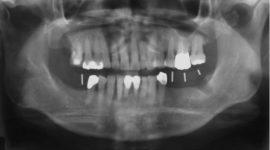

Sterowana regeneracja kości. Poszerzenie wyrostka zębodołowego żuchwy.